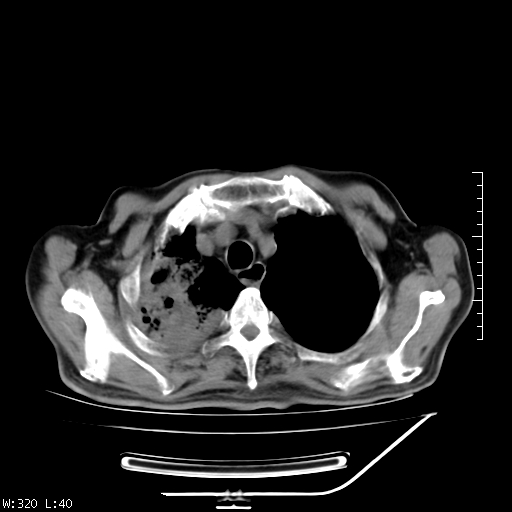

标题: CT23994:男、72、咳嗽、气短两月余,近来消瘦。 [打印本页]

标题: CT23994:男、72、咳嗽、气短两月余,近来消瘦。

右上肺实变,与胸膜关系密切,右肺容积缩小,隆突下淋巴结增大,考虑1 肺结核 2 肺癌

右上肺大片状密度增高影,与胸膜关系密切,内见低密度透亮影,胸膜下可见三角形不张影,左下肺沿支气管走形结节影,纵膈内淋巴结显示。考虑结核并疤痕性不张可能性大,建议穿刺活检,排除肺泡癌。

以下是引用muzi888在2010-1-6 9:43:00的发言:[br]右上肺实变,与胸膜关系密切,右肺容积缩小,隆突下淋巴结增大,考虑1 肺结核 2 肺癌